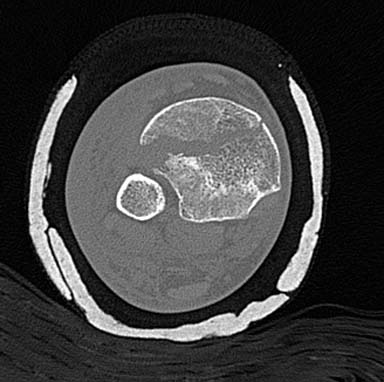

Первый случай, где перелом в результате падения с  небольшой высоты, где

мортиз рентген снимок показал отстутствие укорочения наружной

лодыжки и КТ срезы подсказали направления атаки. После такой фиксации

нет надобности в гипсовой повязке, брейс и через две недели движения в

суставе без нагрузки.